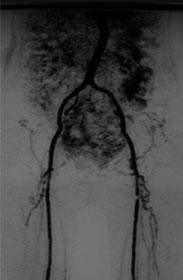

MRA

ABI:右 0.59 左 0.59

当日 皆さまと決めましょう

その際の下肢動脈造影にて右EIA狭窄と両側SFAのCTOを認めた(Lt>Rt)。